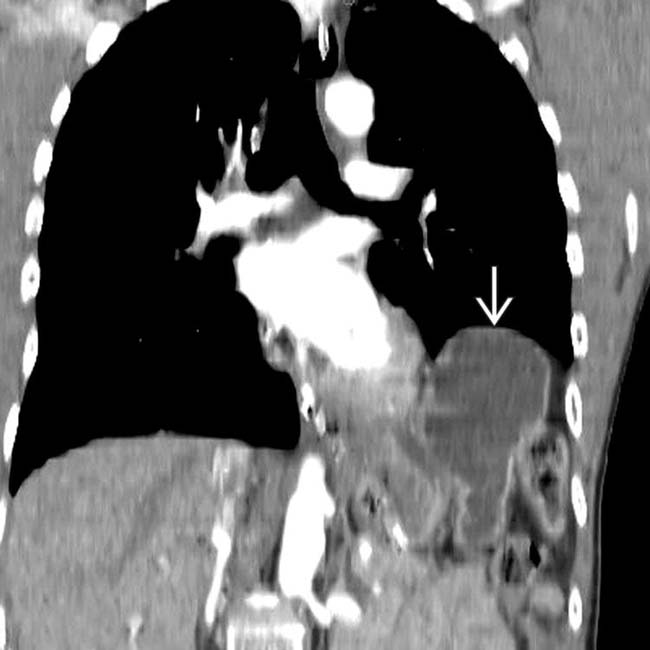

From radiopaedia.org

Traumatic diaphragmatic rupture Image Diaphragm Rupture Meaning More common in penetrating trauma. — suspect if wound tract may extend between t4 and t12 levels. It is usually caused by penetrating trauma or blunt. In diaphragmatic rupture, abdominal contents herniate through a diaphragm weakened by congenital defects or abdominal or chest trauma. Rupture of the diaphragm is a condition in which the diaphragm, a sheet of muscle that. Diaphragm Rupture Meaning.